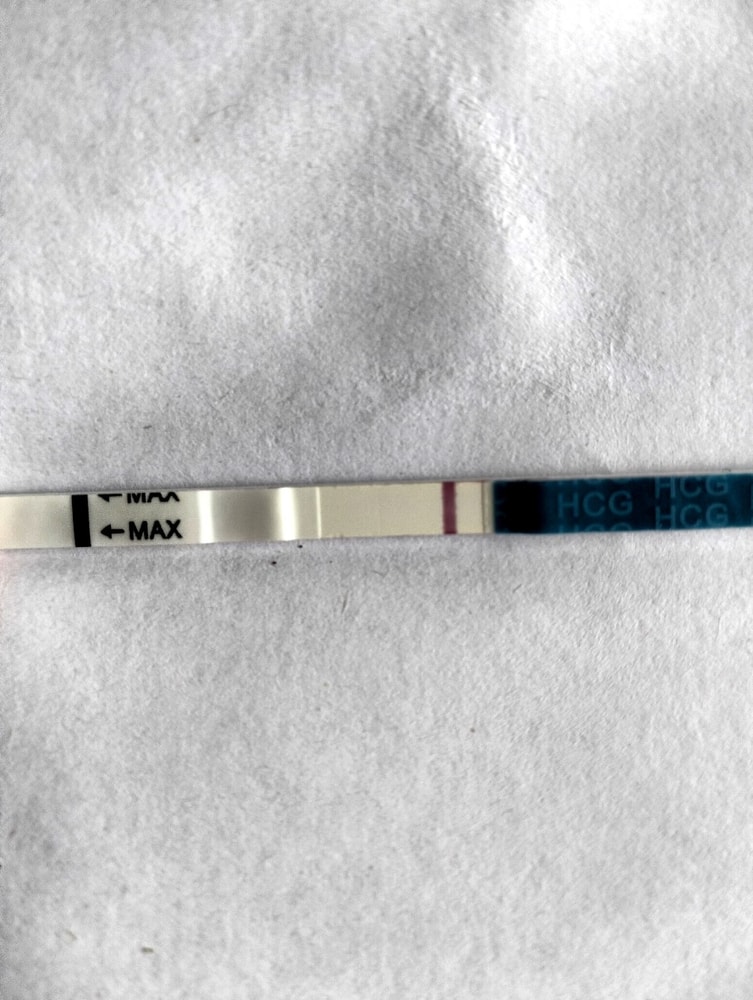

Я читала, что тесты на о показывают б. Возможно ли что и микроскоп на о, показал б.

Я уже ловила о в этом цикле, а по бт поймала из, ну как я думала, как тут вдруг. Вторая о или это первый признак б. Давайте попробуем разобраться. Подобного я р